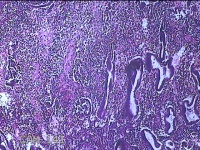

性别

女

年龄

41岁

临床诊断

异常子宫出血(无排卵型子宫出血) 子宫肌瘤

一般病史

阴道流血12天。

标本名称

宫腔内容物

大体所见

灰白暗红色不规则碎组织2.5x2x0.8cm一堆。

图3